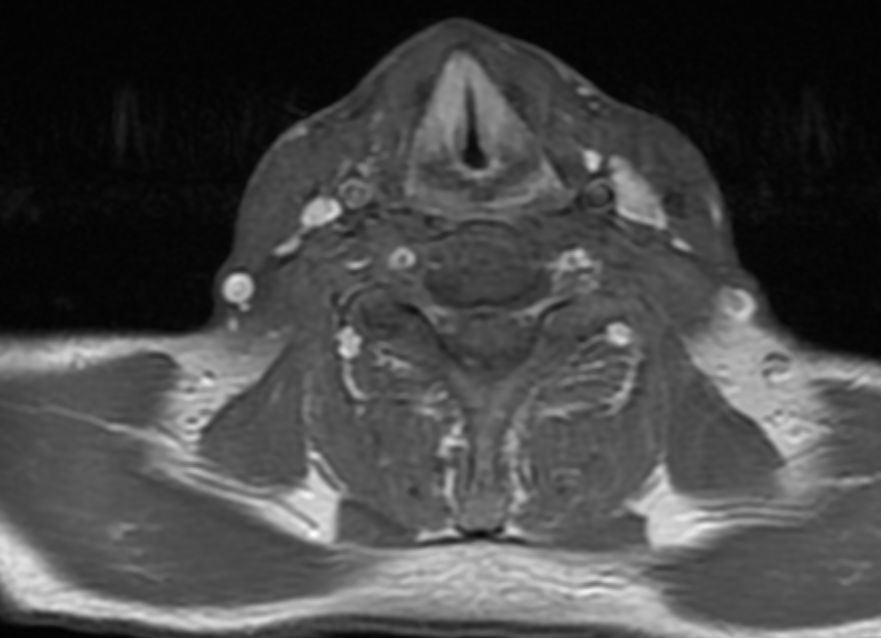

MRT: supraglottisch T3 No |

57-jähriger Mann mit langjährigem Alkohol- und Nikotinabusus. Seit 6 Monaten Schluckbeschwerden. Jetzt zunehmende Kachexie. MRT: Ausgedehntes supraglottisches Larynxkarzinom mit Schildkrorpel-Infiltration. Kehlkopfteilresektion mit ND. Histologie: unverhornendes Plattenepithelkarzinom, V0 R1 G1 - 2 Stadium post OP: pT3 pN0 (0/7) M0 | ||